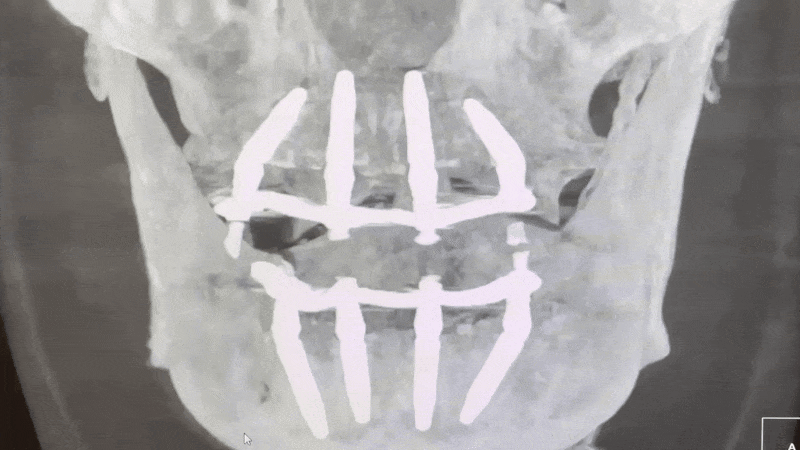

У пациента были удалены все зубы и сразу установлены по четыре дентальных импланта Straumann на обе челюсти. Операция длилась четыре часа под общей анестезией с ИВЛ и прошла без каких-либо осложнений, под контролем анестезиолога. Все имплантаты достигли своего уровня торка, обеспечив высокую первичную стабилизацию.

Визуализация КЛКТ